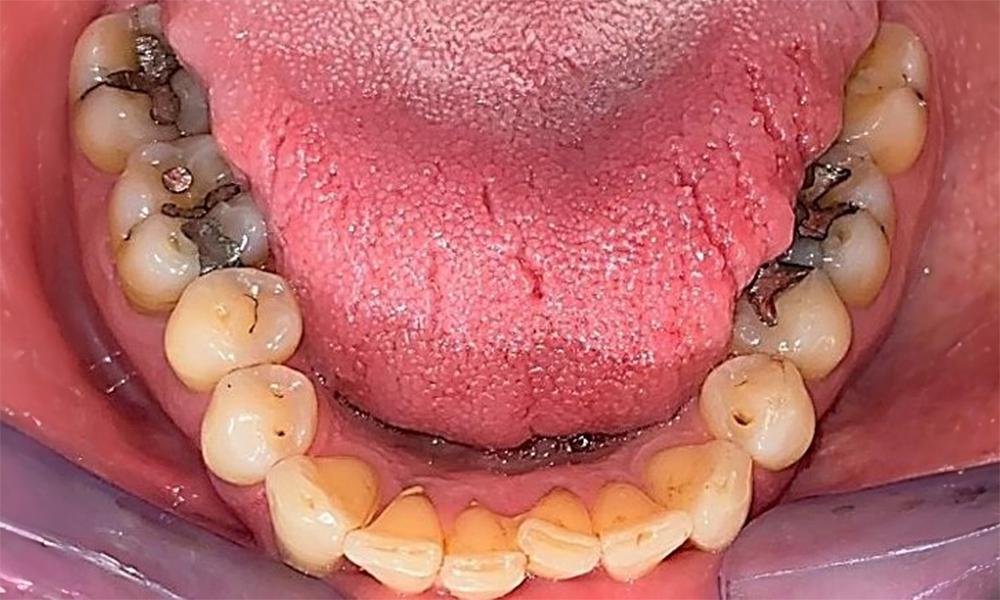

Пациентът има пълно съзъбие с 28 зъба, което включва амалгамни и композитни пломби в областта на моларите и премоларите. На зъб 14 има видима клинична маргинална празнина. Зъб 27 има адекватна златна инкрустация. Налице са и генерализирани атриции и абразии. (фиг. 2, фиг. 3, фиг. 4, фиг. 5, фиг. 6)

Пациентът е с пародонтит II стадий, степен В (5). Клиничните дълбочини на сондиране от 1 до 3 mm са във физиологичния диапазон. Локализирани дълбочини на сондиране от 5 mm са наблюдавани медиопалатинално на 17 и 27. Налице са генерализирани рецесии от 1 до 3 mm с частична загуба на интердентални папили (фиг. 2, фиг. 3, фиг. 4)